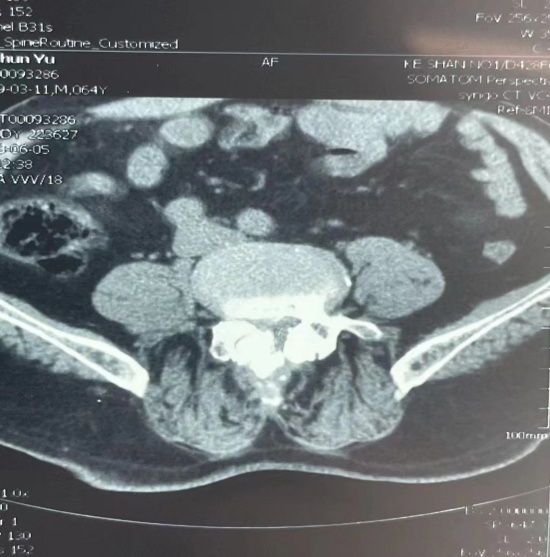

患者术前CT片子

经诊断,该患者 L4/5重度椎管狭窄,骨外一科负责人辛兆旭带领主治医师赵越及全体医生展开术前讨论,决定为李先生进行脊柱微创 UBE手术。